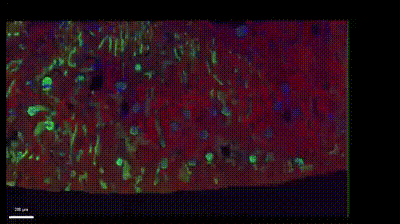

(癌癥組織6色成像)

THUNDER結(jié)合上游的多色熒光染色技術(shù),如TSA技術(shù),突破常規(guī)熒光標(biāo)記方法因?yàn)榉N屬限制和特異性限制,可以實(shí)現(xiàn)超過(guò)4色的細(xì)胞生物學(xué)研究。通過(guò)多個(gè)熒光探針(或多個(gè)熒光蛋白)對(duì)不同的生物分子或細(xì)胞結(jié)構(gòu)進(jìn)行標(biāo)記,可以同時(shí)觀察多個(gè)目標(biāo),并了解它們之間的相互關(guān)系和空間分布,揭示細(xì)胞內(nèi)的亞細(xì)胞結(jié)構(gòu)、細(xì)胞類型、代謝狀態(tài)、信號(hào)通路活性等多個(gè)方面的信息。